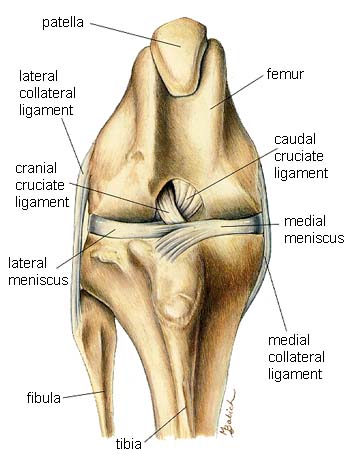

The musculoskeletal system includes all the muscles, bones and joints.

- Stifle (knee)

Stifle (knee)